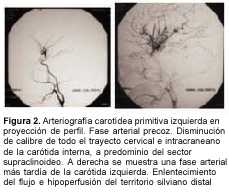

Hasta el advenimiento de las nuevas técnicas de angiorresonancia, el diagnóstico definitivo se hacía exclusivamente con la arteriografía cerebral. Esta es de utilidad para definir la topografía y extensión de las oclusiones. Los hallazgos angiográficos se caracterizan por lesiones que afectan predominantemente la circulación anterior, y que son: en la fase temprana del estudio, disminución del calibre de las carótidas internas intracranealas y del sector proximal de los vasos del círculo de Willis, y desarrollo de colaterales lenticuloestriadas y talamoperforantes ("vasos de moyamoya"). En la fase intermedia la imagen de "nube" o "humareda". Y en la fase tardía el desarrollo de colaterales transóseas y transdurales. El desarrollo de todas estas colaterales es consecuencia de la oclusión carotídea.

A los 3 meses de edad consultó por hemiplejia izquierda y retraso psicomotor. La tomografía computada (TC) de cráneo demostró un infarto hemisférico derecho (figura 1). Los estudios complementarios pusieron de manifiesto una coartación de aorta torácica descendente, sin evidencia de patología arterial sistémica. A nivel encefálico se estudió con angiografía de cuatro vasos de cuello, que demostró la existencia de una enfermedad de moyamoya (figuras 2 a 4). En ese momento no se consideró el tratamiento quirúrgico y una vez estabilizada se otorgó el alta. La coartación de la aorta no requirió cirugía y no se investigó el eventual nexo con la enfermedad de moyamoya. A los 8 meses de edad comenzó con hemiparesia derecha progresiva, lo que junto a su hemiplejia izquierda agravó su déficit motor severamente. Ingresó al Centro Hospitalario Pereira Rossell a los 10 meses. El examen del ingreso mostraba retardo neuropsíquico, hemiplejia izquierda espástica y hemiparesia derecha severa, que apenas vencía gravedad y no oponía resistencia. Una nueva TC mostró como elemento agregado al infarto derecho previo, una isquemia hemisférica izquierda (figura 5). Se resolvió realizar una revascularización quirúrgica del hemisferio izquierdo. Se intervino (figura 6) en el Servicio de Neurocirugía Pediátrica del Hospital. El procedimiento realizado fue una pialsinangiosis, con disección de la arteria temporal superficial izquierda con galea satélite y la sutura del tejido periarterial a la aracnoides temporal. La evolución posoperatoria fue buena, con recuperación progresiva de la función motora del hemicuerpo derecho. En forma gradual también comenzó a recuperar motricidad de su hemicuerpo izquierdo, anteriormente pléjico, y a mejorar sus performances, comenzando a pronunciar palabras a los cuatro meses, aunque manteniendo un retraso en el desarrollo psicomotor. Al año de operada se constató leve hemiparesia izquierda, ausencia de elementos deficitarios motores a derecha y persistencia de alteraciones en el lenguaje. Una ARM realizada a los diez meses de la operación mostró desarrollo de circulación colateral hacia el área quirúrgica (figura 7). Una TC de control permitió ver el infarto secuelar de hemisferio derecho y disminución franca de la hipodensidad del hemisferio izquierdo a los 18 meses de operada (figuras 8 y 9).

En una primera etapa, a los 3 meses de edad, la paciente fue encarada como un stroke en el lactante, y fue estudiada en ese sentido. Se fueron descartando las causas habituales hasta que se llegó al diagnóstico de enfermedad o síndrome de moyamoya con la angiografía. De acuerdo con las normas diagnósticas del cuadro 1, el caso debía ser catalogado como definitivo por la presencia de los ítems A y C. En ese momento no se consideró oportuno el tratamiento quirúrgico.